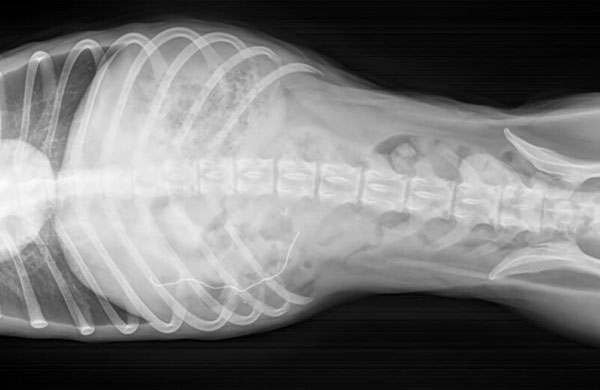

Un perro a punto de perder su vida tras comerse una mascarilla, ha requerido ser operado de urgencia.

El uso masivo de mascarillas, tras hacerse su uso obligatorio en muchos países puede tener consecuencias inesperadas. Así lo está advirtiendo el Animal Rescue Leage, un refugio para animales de Boston, tras comprobar lo ocurrido a uno de sus perros. De nombre Gibbs, este pequeño perro mezcla de fox terrier ha tenido que ser operado de urgencia tras comerse una mascarilla quirúrgica.

En el refugio explican que a menudo las mascarillas huelen ligeramente a comida, por estar en contacto tan directo con el aliento y la boca de las personas que las llevan, y ese mínimo rastro de alimento es suficiente para que algunos perros opten por comérselas. En este caso, Gibbs, ha logrado sobrevivir, gracias a una intervención a tiempo, sin embargo, en otros casos sin tratamiento, el resultado será la muerte del perro. La mascarilla en sí puede causar una obstrucción intestinal y quedarse atascada en las tripas del perro, y la parte metálica inserta en el reborde superior puede llegar a perforar el tejido blando.